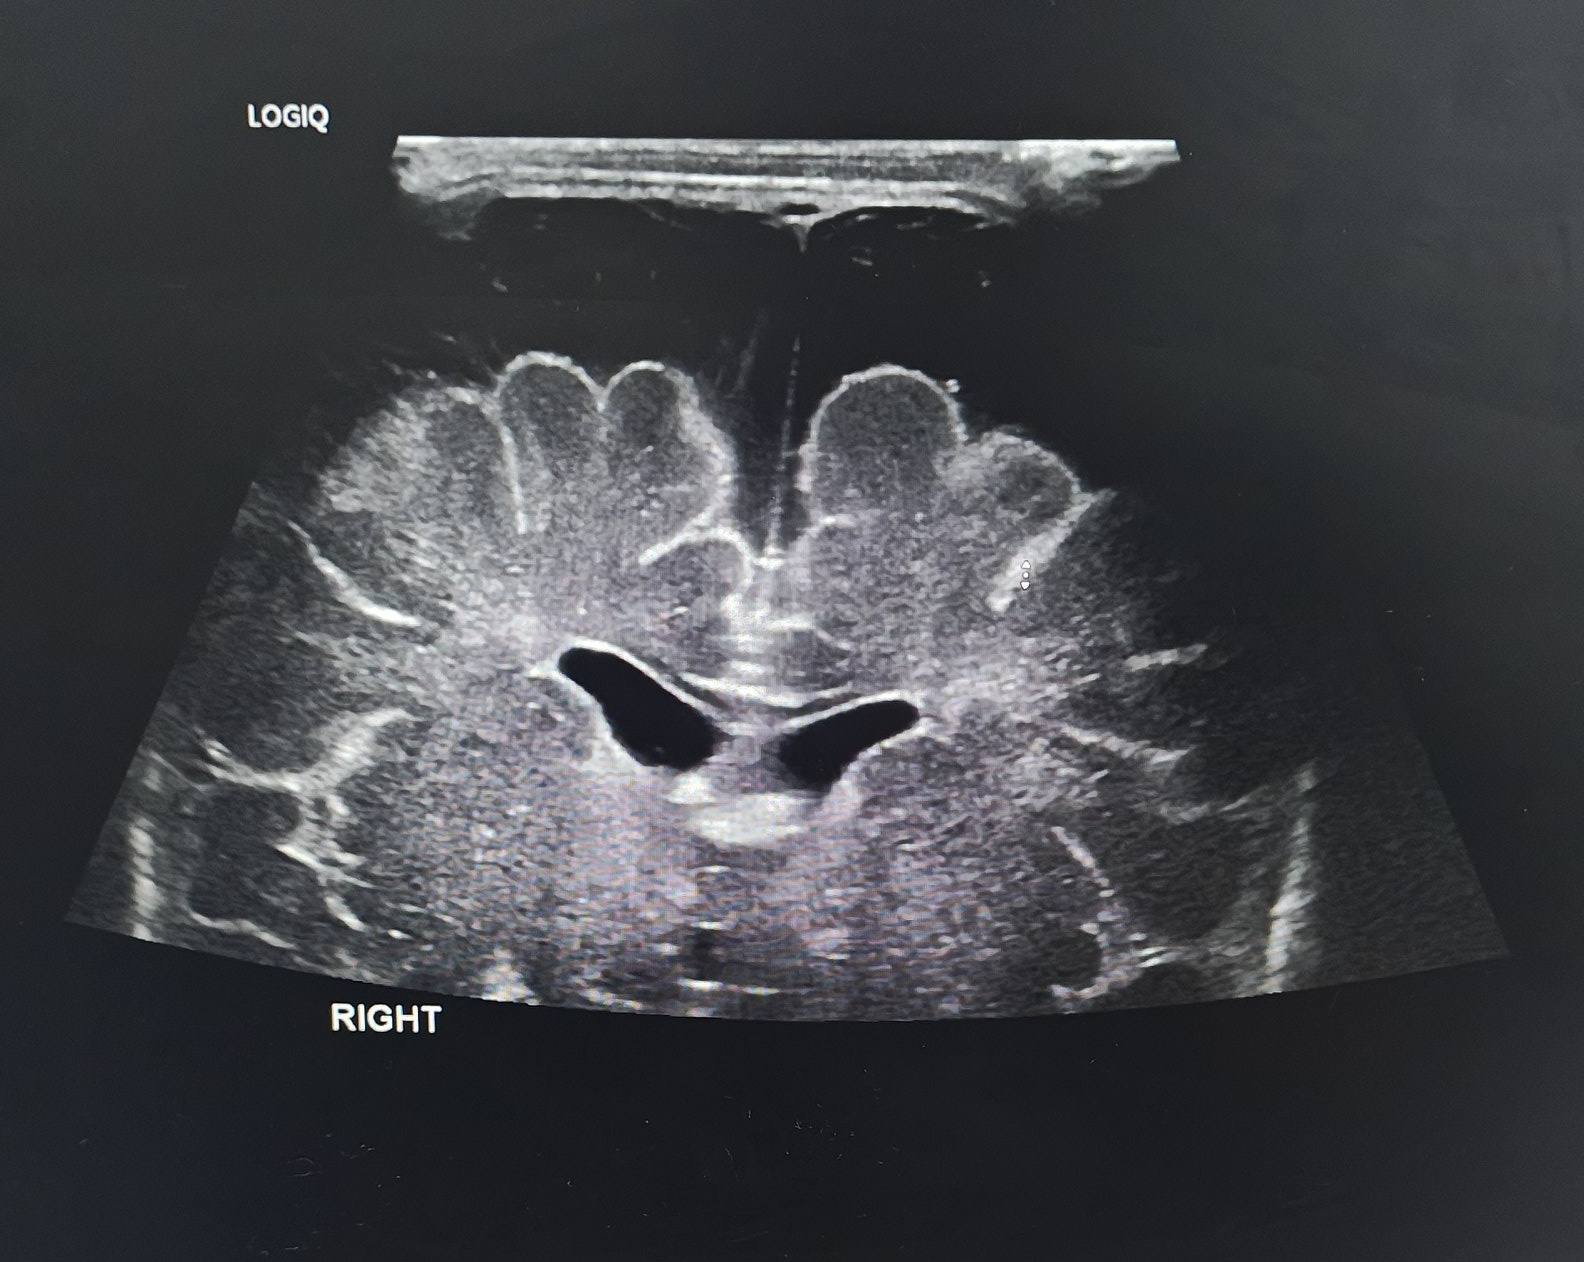

Doctors and family members are closely monitoring a newborn boy named Noah, who remains under intensive medical care as he faces a serious brain tumor diagnosed shortly after birth. Born significantly underweight and physically fragile, Noah is spending his earliest days surrounded by medical equipment, guided by constant care and quiet determination.

Medical specialists have explained that treating a brain tumor in a newborn presents exceptional challenges due to the baby’s size and developing body. While the road ahead remains uncertain, the care team is focused on keeping Noah stable and as comfortable as possible while evaluating next steps.